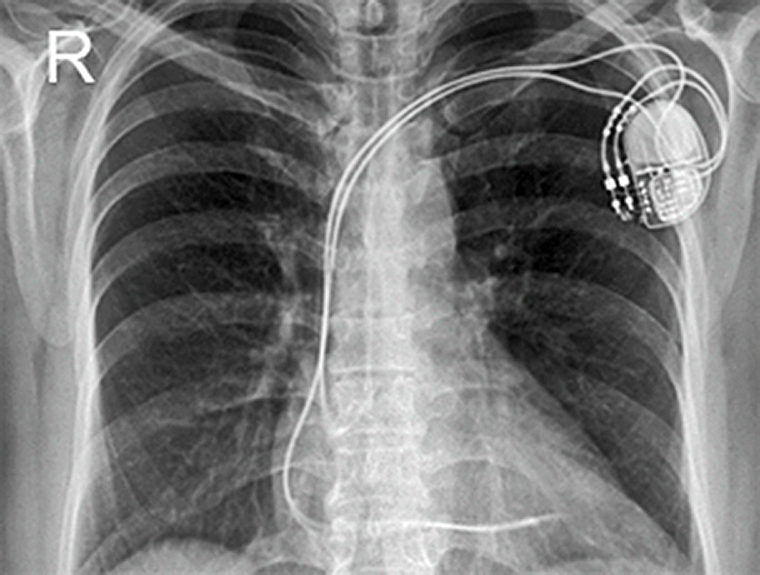

Any new method in medicine, be it diagnostic or therapeutic, must be tho­­rou­gh­ly checked for possible adverse effects — and magnets can have fatal at­trac­tions (Figure 18-01).

Figura 18-01:

Magnets can have fatal attractions — whether it is low field or high field.

spaceholder redThere is a wide range of incidental dangers that can lead to accidents (Figures 18-01 and 18-02). Three groups of accidents responsible for more than 90% of all re­port­ed injuries to patients and per­­son­nel. Nearly all accidents are incidental, caus­ed by negligence — by staff or patient — or the em­ploy­ment of in­ap­pro­pri­­ate or un­suit­able equipment or devices. The most common hazards of MR imaging are:

spaceholder redThe number of contraindications for MR imaging, functional MR, MR spec­tro­sco­py, and similar techniques has decreased during the last years. In many instances patient-related devices have been adapted for MR imaging purposes. The con­­tra­in­di­ca­tions may change from country to country or at different jurisdictions, but ad­he­ren­ce to them is strongly recommended. Earlier distinction be­tween absolute and relative con­tra­in­di­ca­tions has been replaced by the term "Poten­tial Con­tra­in­di­ca­tions". These include:

spaceholder darkblueElectronically, magnetically, and mechanically activated implants: cardiac pace­makers and implantable cardioverter defibrillators;

spaceholder darkbluelead wires or similar wires;